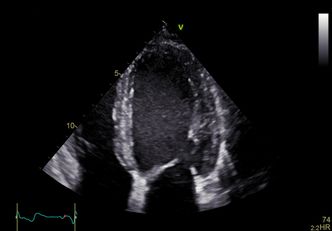

Ultralydmaskiner sender høyfrekvent lyd inn i kroppen og fanger opp ekkoene, som omdannes til visuelle bilder av organenes form.

Programvaren cSound plukker de beste signalene og setter det sammen til et svært presist og godt bilde i sanntid, kontinuerlig. Altså ikke bare 2D og 3D, men 3D i sanntid, gjerne kalt 4D.

Hjertekirurg Bijoy Khandheria ved Aurora St. Luke's Medical Center i Milwaukee, sier at det er som å se hjertet i "ekstrem 4D" med Vivid E95.

– Bildene er helt fantastiske. Det er som åpne brystkassen og se rett inn på hjertet som slår, sier han i en pressemelding.

Han sier at man kan se blodstrømmen og strømningsvirvlene rundt propper i arteriene. Det gir uvurderlig informasjon til kirurgene før operasjon.